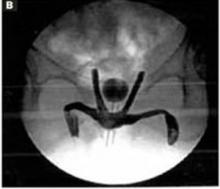

FIGURE 10 Routes of transobturator and retropubic slings

Graphic depiction of both the transobturator sling and the retropubic tension-free sling in place.

Fluoroscopic image of both slings in a cadaver. The transobturator sling runs horizontally while the retropubic tension-free sling forms a tighter “U.”